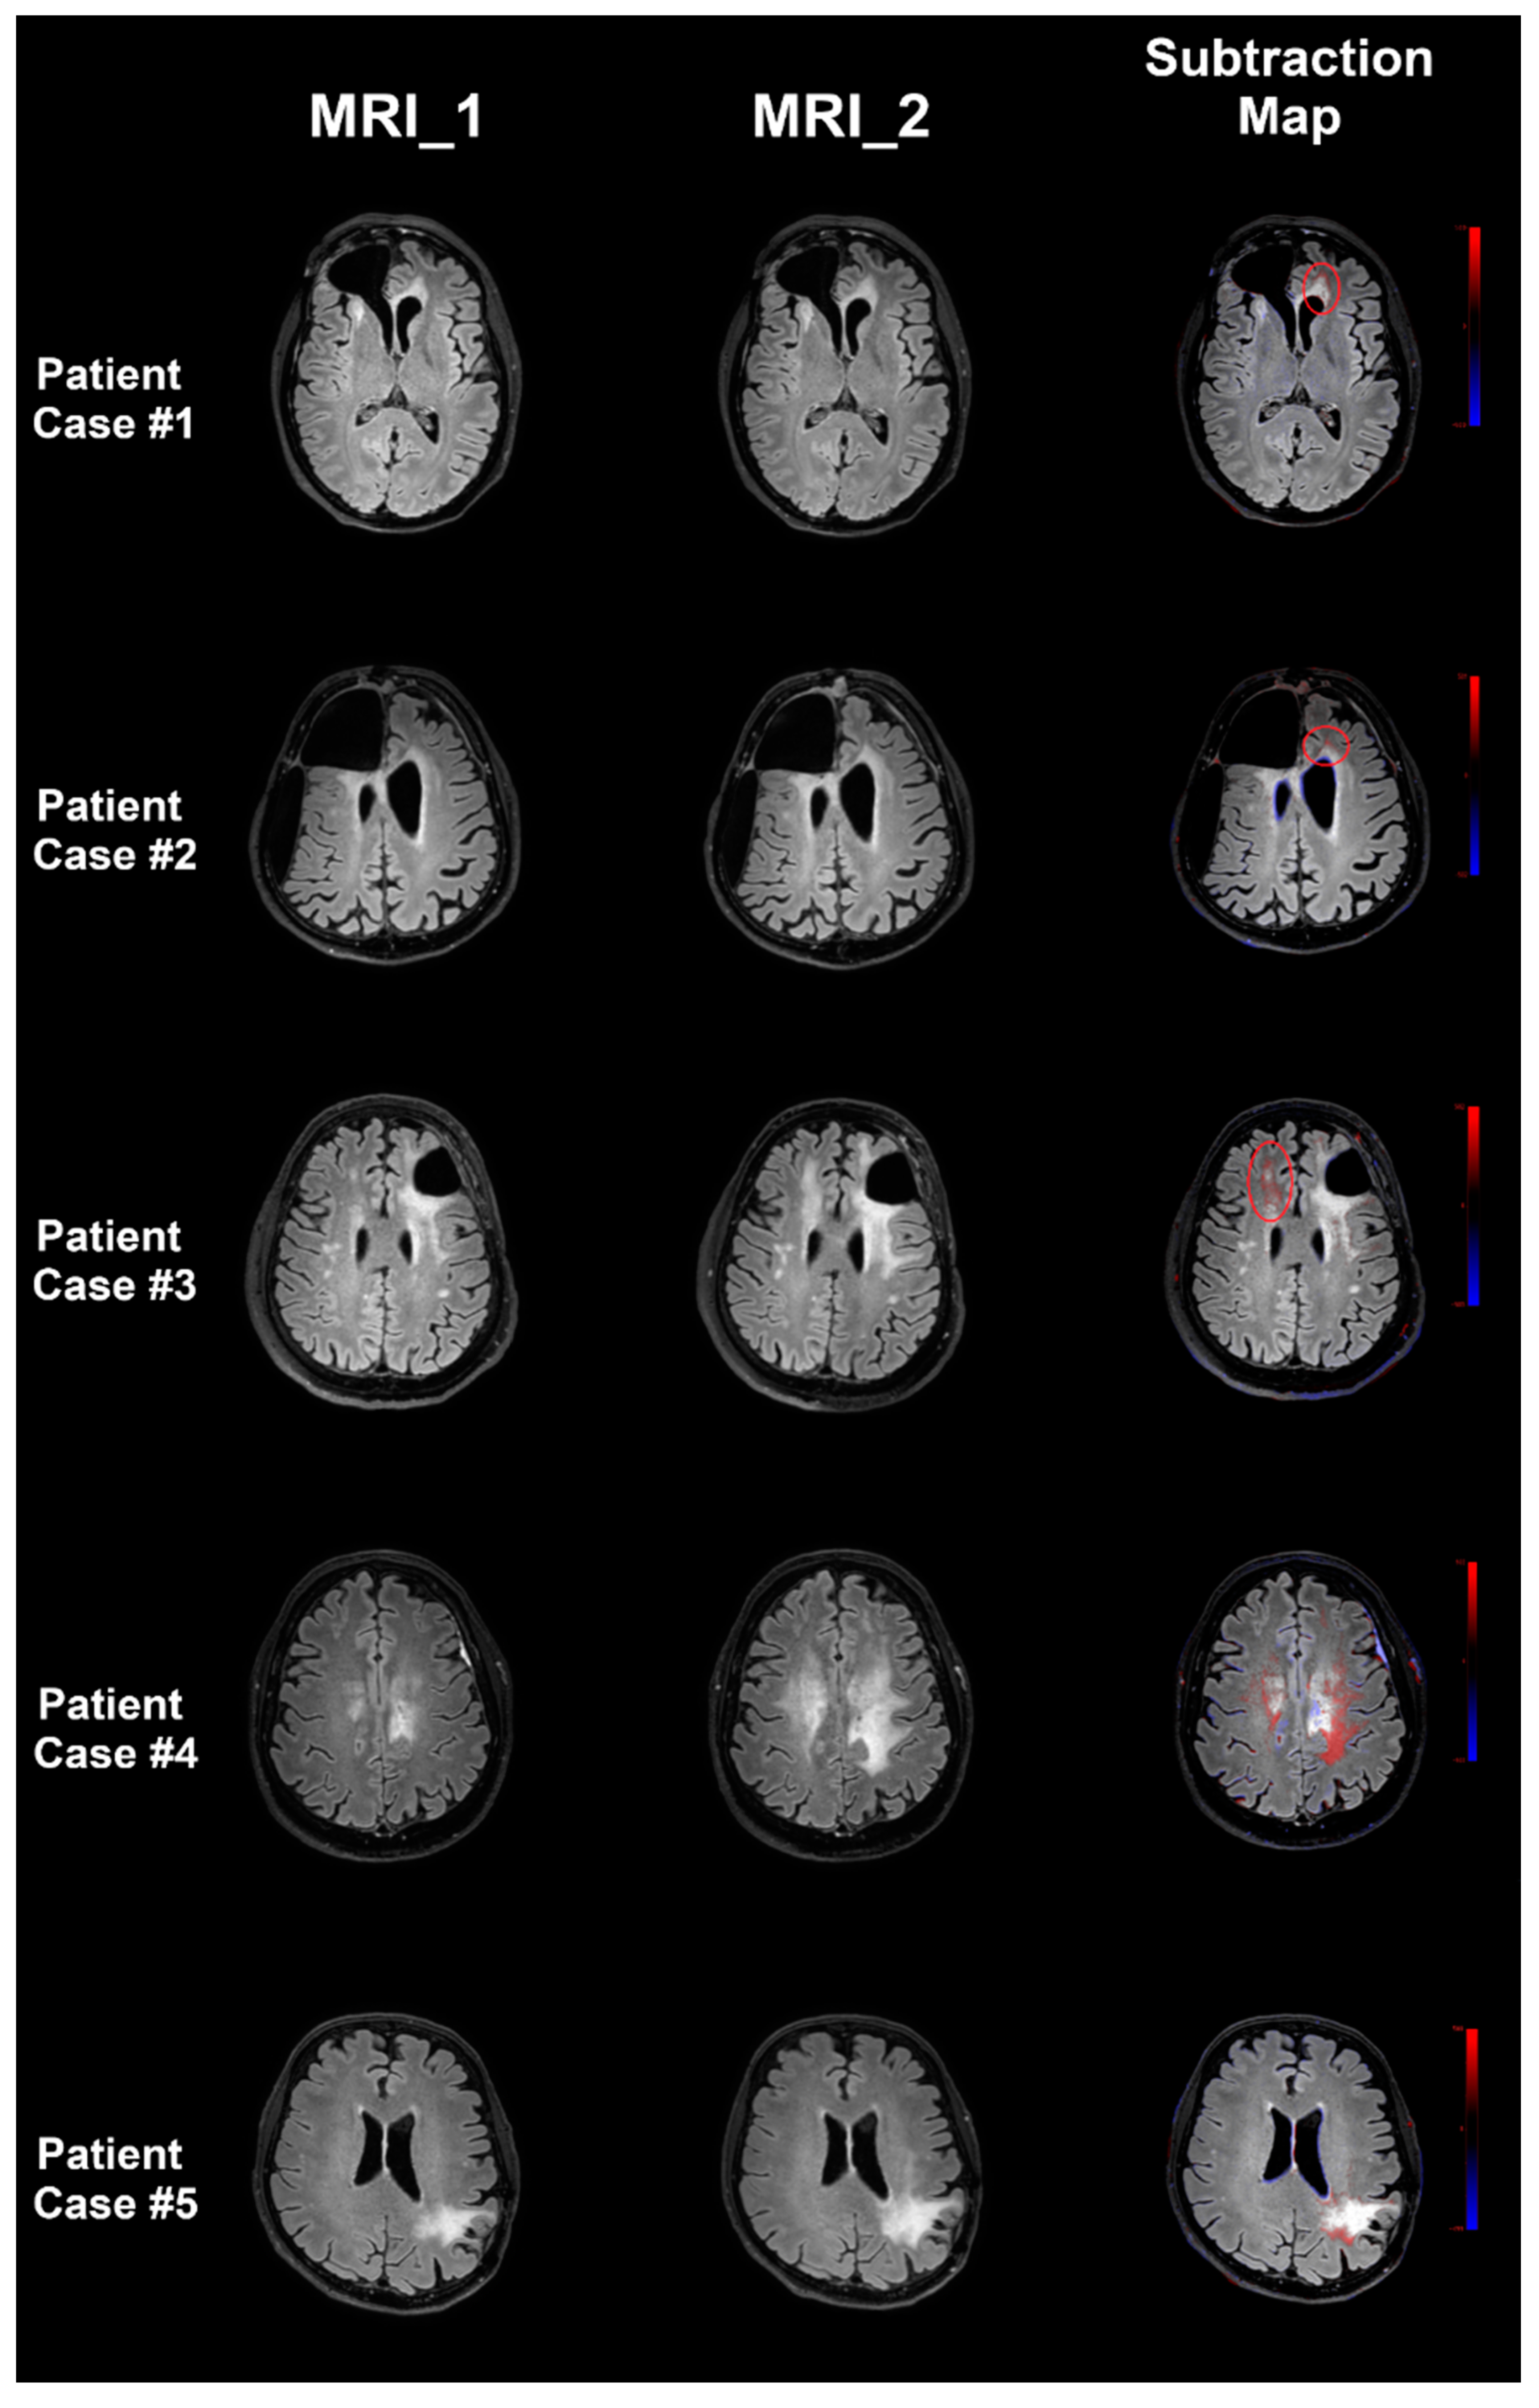

Subtraction Maps Derived from Longitudinal Magnetic Resonance Imaging in Patients with Glioma Facilitate Early Detection of Tumor Progression

- Lennartz, S.; Zopfs, D.; Nobis, A.; Paquet, S.; Hoyer, U.C.I.; Zaske, C.; Goertz, L.; Kabbasch, C.; Laukamp, K.R.; Grosse Hokamp, N.; et al. MRI Follow-up of astrocytoma: Automated coregistration and color-coding of FLAIR sequences improves diagnostic accuracy with comparable reading time. J. Magn. Reson. Imaging 2020, 52, 1197–1206. [Google Scholar] [CrossRef] [PubMed]

- Patel, N.; Horsfield, M.A.; Banahan, C.; Thomas, A.G.; Nath, M.; Nath, J.; Ambrosi, P.B.; Chung, E.M.L. Detection of focal longitudinal changes in the brain by subtraction of MR images. Am. J. Neuroradiol. 2017, 38, 923–927. [Google Scholar] [CrossRef] [PubMed]